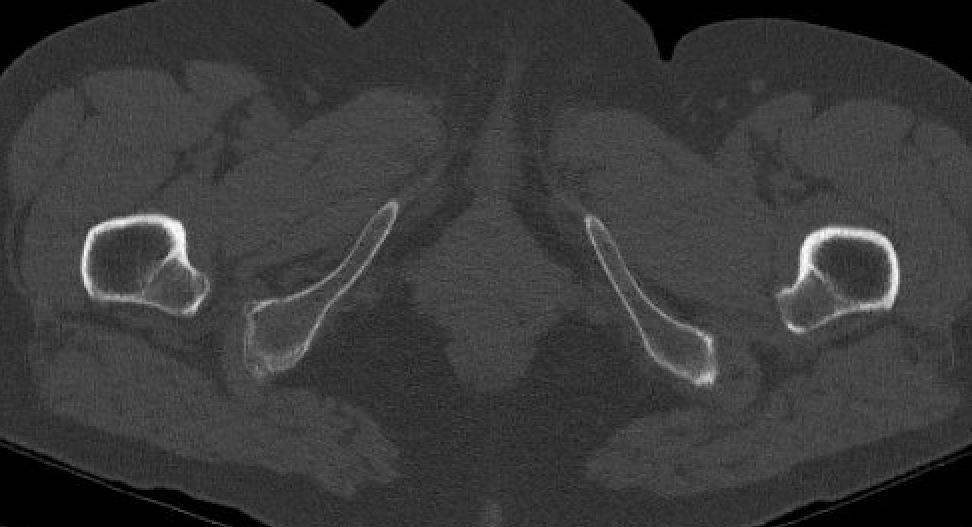

Definition

Narrowing of the ischiofemoral space between lateral ischium and lesser trochanter

Entrapment / compression of quadratus femoris

Reduced ischiofemoral space - distance between the lesser trochanter and the ischial tuberosity

Reduced quadratus femoris space - distance between hamstring tendon and iliopsoas

CT